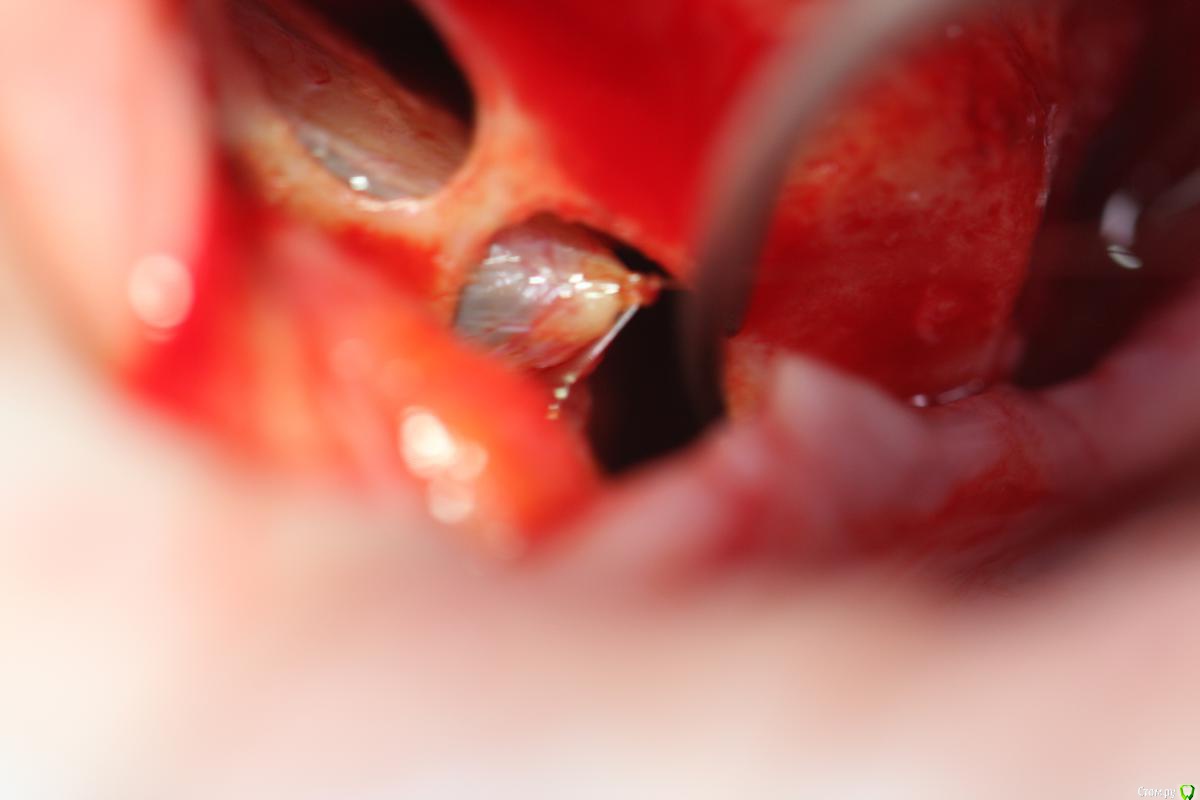

Rafael_Gogyan Опубликовано 5 октября, 2016 Поделиться Опубликовано 5 октября, 2016 (изменено) http://s017.radikal.ru/i413/1610/a0/f15e3aa84072.jpg http://s017.radikal.ru/i443/1610/61/22c536a171c3.jpg это то, что попало в камеру на последнем фото слизистая пришита к костной стенке Изменено 5 октября, 2016 пользователем Rafael_Gogyan 5 Ссылка на комментарий